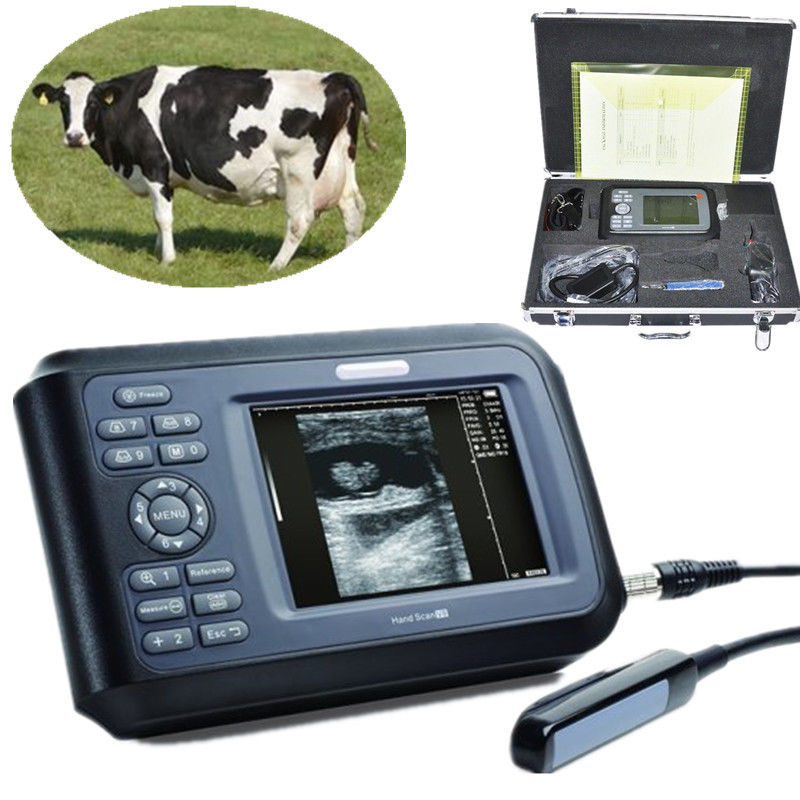

Gift 3D Vet Veterinary Digital Ultrasound Scanner Monitor Micro-Convex Probe USB

Sale price$ 1,980.29

Regular price$ 2,414.99

Gift+Pro 5.5'' Vet LCD Color Digital PalmSmart Ultrasound Scanner+Rectal Probe 190891940223

Sale price$ 1,436.63

Regular price$ 1,751.99